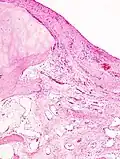

While osteoarthritis is a degenerative joint disease that may cause gross cartilage loss and morphological damage to other joint tissues, more subtle biochemical changes occur in the earliest stages of osteoarthritis progression. The water content of healthy cartilage is finely balanced by compressive force driving water out and hydrostatic and osmotic pressure drawing water in.[37][38] Collagen fibres exert the compressive force, whereas the Gibbs–Donnan effect and cartilage proteoglycans create osmotic pressure which tends to draw water in.[38]

However, during the onset of osteoarthritis, the collagen matrix becomes more disorganized, and there is a decrease in proteoglycan content within cartilage. The breakdown of collagen fibers results in a net increase in water content.[39][40][41][42][43] This increase occurs because whilst there is an overall loss of proteoglycans (and thus a decreased osmotic pull),[40][44] it is outweighed by a loss of collagen.[38][44]

Other structures within the joint can also be affected.[45] The ligaments within the joint become thickened and fibrotic, and the menisci can become damaged and wear away.[46] Menisci can be completely absent by the time a person undergoes a joint replacement. New bone outgrowths, called "spurs" or osteophytes, can form on the margins of the joints, possibly in an attempt to improve the congruence of the articular cartilage surfaces in the absence of the menisci. The subchondral bone volume increases and becomes less mineralized (hypo mineralization).[47] All these changes can cause problems functioning. The pain in an osteoarthritic joint has been related to thickened synovium[48] and to subchondral bone lesions.[49]